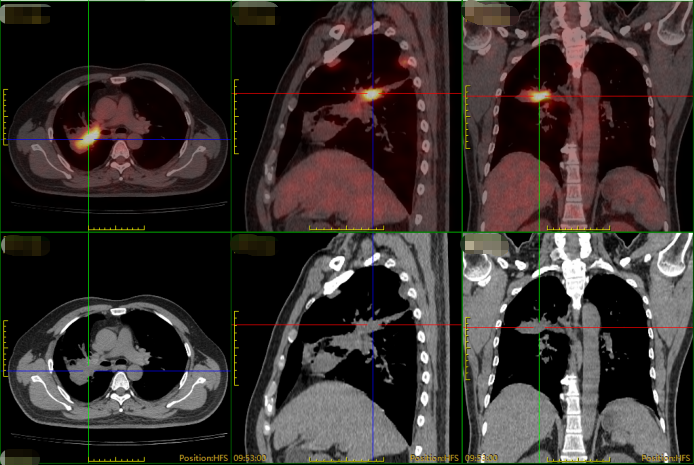

然而,进一步的PET-CT检查显示,他的病情已属晚期(T4N3M1),肿瘤侵犯广泛,并已发生转移(右侧胸膜、叶间裂及右肺多发小结节,考虑转移,病灶累及右肺动静脉可能,伴右肺门、纵隔(2R/L、4R、7组)、双侧锁骨上窝淋巴结转移)。

右肺上-中叶近肺门区软组织密度肿块影,FDG 摄取增高